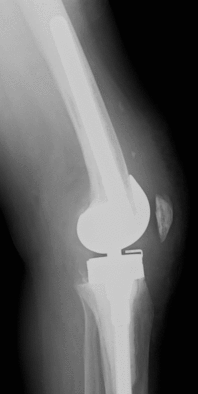

Teilprothese oder Schlittenprothese

Bei diesem Prothesenmodell wird nur der geschädigte innere, selten äußere Teil des Kniegelenkes ersetzt. Voraussetzung ist, dass eine Gelenkhälfte und das Kniescheibengelenk intakt sind, und stabile Bänder ohne höhergradige Bewegungseinschränkung vorliegen. Häufig wird diese Teilprothese bei isoliertem innenseitigen Knieverschleiß eingesetzt.

Das deutlich kleinere Implantat im Vergleich zur Vollprothese ermöglicht weichteilschonende Operationstechniken und kleinere Zugänge sowie einer schnellere Rehabilitation.